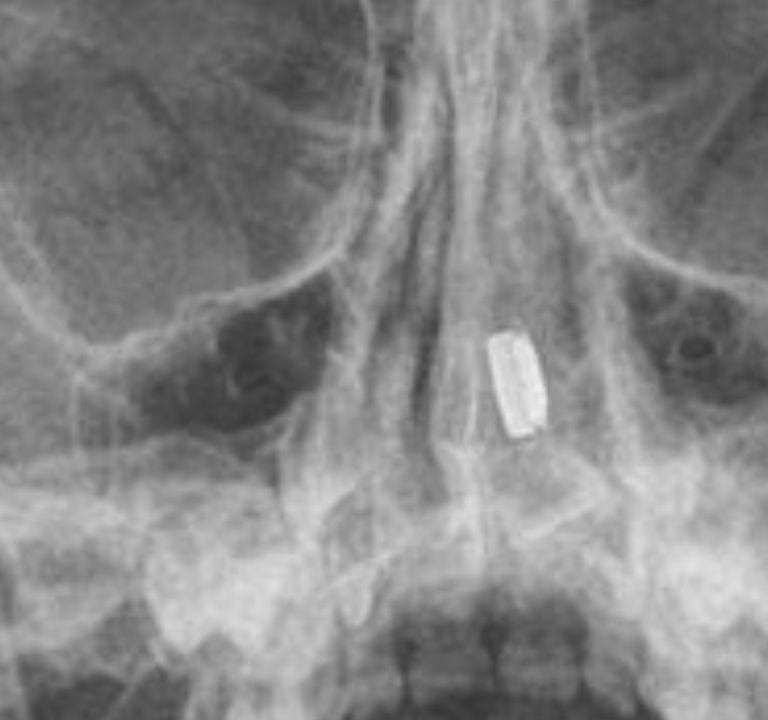

X-rays: Used in some cases to locate metallic objects like button batteries.

Tip: Avoid attempting removal at home unless you’re certain it’s safe.